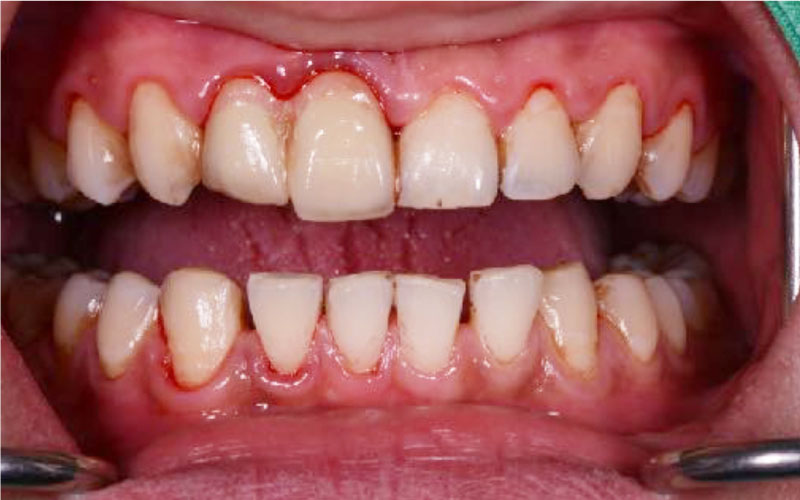

美白前

美白後